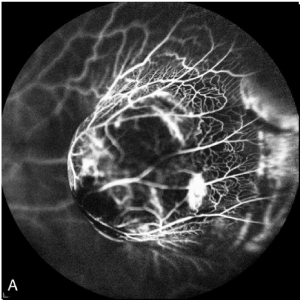

Fluorescein and indocyanine Angiography (FA + ICG-A) was performed and displayed the presence of an irregularly pigmented choroidal lesion and an hyperfluorescence with atypical circulation (Figures 4A and 4B). Optical coherence tomography showed a detachment of the neuroepithelium (Figure 5).

Figure 4A. Fluorescein Angiography. irregularly pigmented choroidal lesion